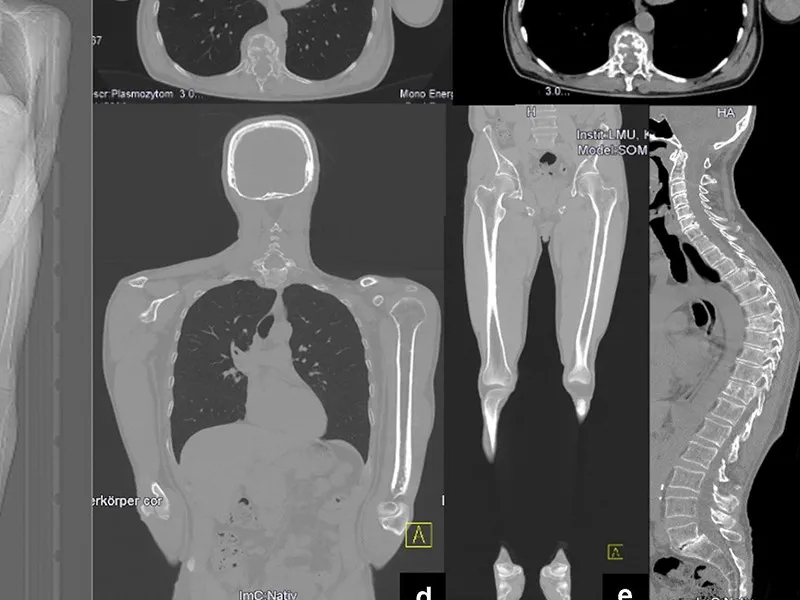

Tüm vücut MR, manyetik rezonans görüntüleme teknolojisi kullanılarak vücudun tamamının ayrıntılı bir şekilde taranmasıdır. Radyasyon içermeyen bu yöntem, manyetik alan ve radyo dalgaları yardımıyla organların ve dokuların yapısını detaylı bir şekilde gösterir. Doktorlar, bu görüntüleri kullanarak hastalıkları teşhis eder ve tedavi planlarını oluşturur.

Tüm vücut MR, genellikle hastalıkların erken teşhisi ve yayılımının değerlendirilmesi amacıyla çekilir. Özellikle kanser taramaları, inflamatuar hastalıklar, enfeksiyonlar ve dejeneratif hastalıkların tespitinde kullanılır. Ayrıca, vücutta mevcut olan anormalliklerin detaylı bir şekilde incelenmesi için de tercih edilir.

Tüm vücut MR ile kanser türleri, tümörlerin yayılımı, inflamatuar hastalıklar, enfeksiyonlar, dejeneratif hastalıklar, sinir sistemi bozuklukları ve damar hastalıkları teşhis edilebilir. Bu yöntem, özellikle erken teşhis gerektiren hastalıklarda büyük önem taşır ve doktorların doğru tedavi yöntemini belirlemelerine yardımcı olur.

Tüm Vücut Emar için kullanılan MR Cihazlarımız en yeni teknolojiye sahip 3 Tesla özelliğine sahiptir. Tüm Vücut Emar yüksek çözünürlüklü ve çok net görüntüler doğru teşhis için son derece önemlidir. Tüm Vücut emar için anestezili seçenekler de mevcuttur.